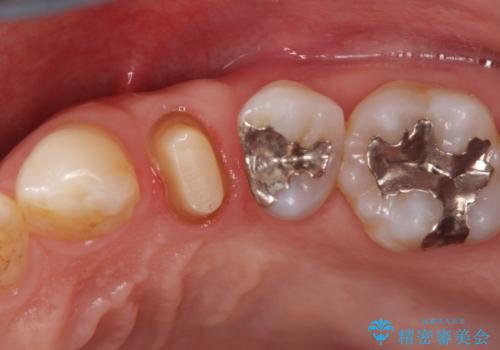

- 歯肉の下まで深く歯が折れたことを主訴に来院された患者様です。

かかりつけ医にて応急的に修復してますが根本的な治療を希望され、矯正的挺出を行ったのち、歯周外科を行い、歯冠修復をしております。

歯肉縁下の水平破折をきちんと治療するためには時間も費用もかかります。